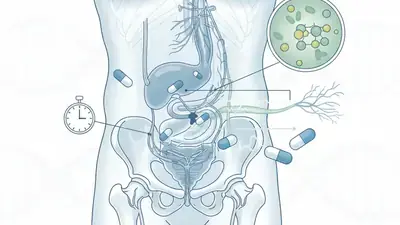

Preparaty, leki i suplementy na potencję

Przedwczesny wytrysk to powszechny problem, który można skutecznie kontrolować. Odkryj oparte na dowodach metody behawioralne, psychologiczne i medyczne, które pomogą Ci odzyskać kontrolę i czerpać więcej satysfakcji z życia intymnego.